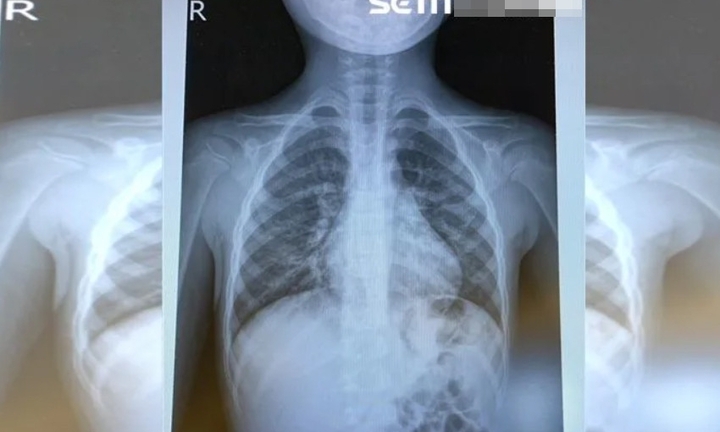

Người dân Trung Quốc đang phải đối mặt với dịch bệnh liên quan virus HMPV, ảnh hưởng nhất đến người cao tuổi và trẻ em.